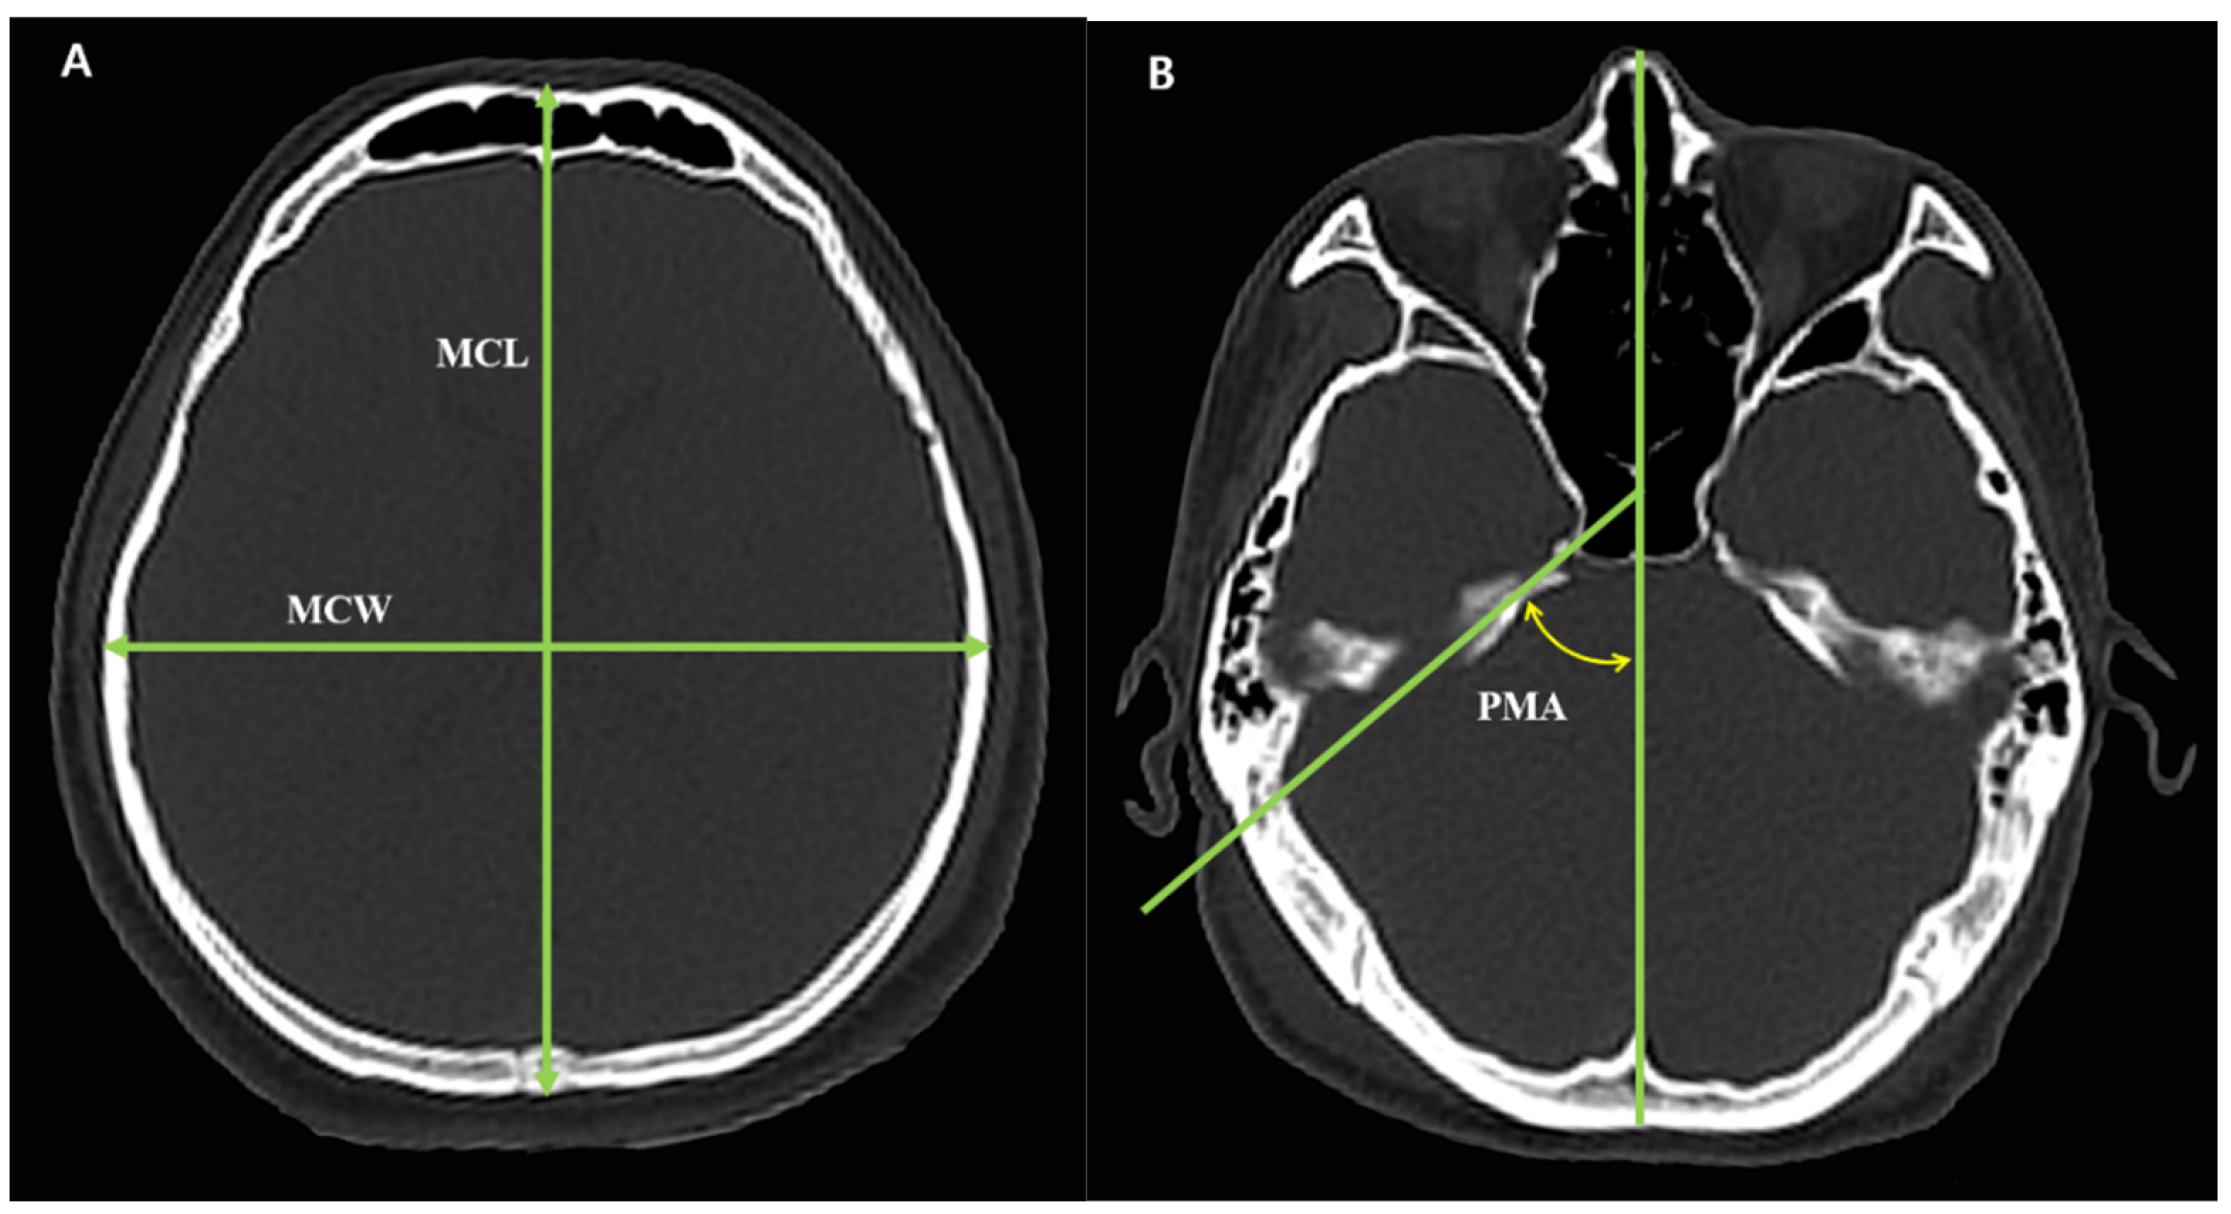

2.3. Cranial Measurement and Morphological Classification

| MCL (mm) | 167.2 ± 8.9 | 166.4 ± 6.9 | 166.8 ± 8.0 | 0.332 |

| MCW (mm) | 142.8 ± 8.7 | 142.8 ± 6.2 | 142.8 ± 7.5 | 0.996 |

| CI (%) | 85.4 ± 4.2 | 85.9 ± 4.8 | 85.7 ± 4.5 | 0.304 |

| PMA (°) | 55.5 ± 2.6 | 54.5 ± 3.1 | 55.0 ± 2.9 | 0.001 |